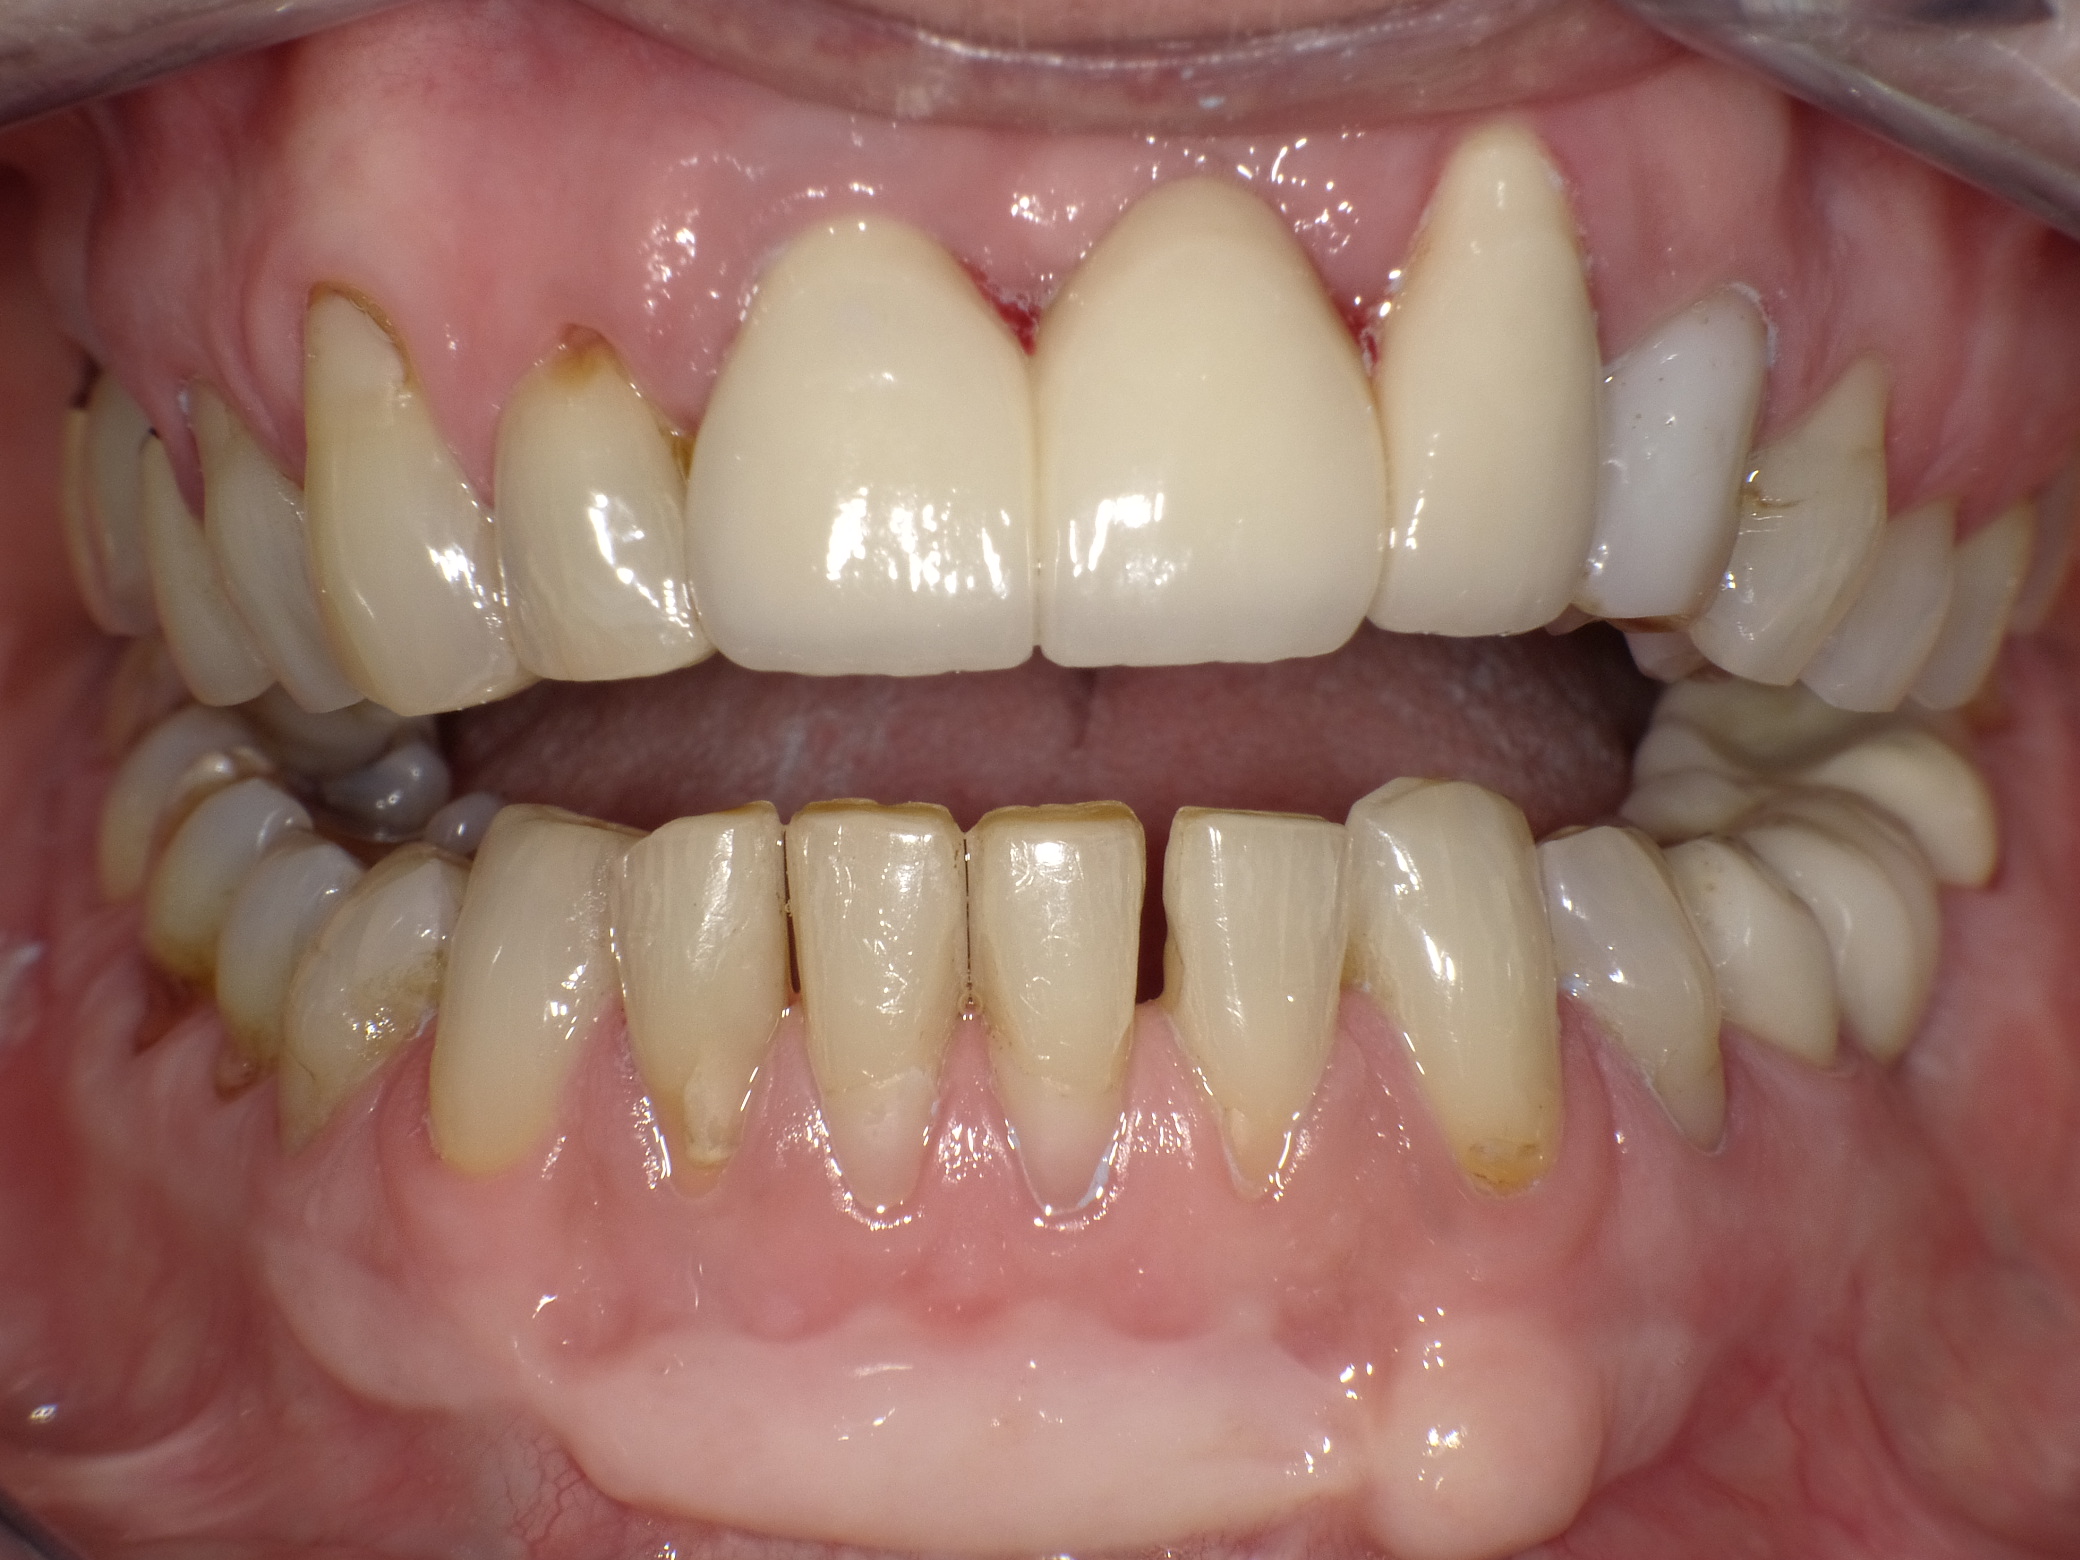

Unbefriedigende Ästhetik, vor allem aber Entzündungen im Knochen und eine massive Parodontitis mit bereits gelockerten Zähnen

Vorher: Unbefriedigende Ästhetik, vor allem aber Entzündungen im Knochen und eine massive Parodontitis mit bereits gelockerten Zähnen

Gesamtbehandlung in Sedierung: die Seitenzähne wurden durch Keramik-Implantate (Zahnentfernungen und Sofortimplantation) mit Knochenaufbau ersetzt; anschließend Gesamtüberkronung aus Vollkeramik mit Optimierung der Ästhetik

Nachher: Gesamtbehandlung in Sedierung: die Seitenzähne wurden durch Keramik-Implantate (Zahnentfernungen und Sofortimplantation) mit Knochenaufbau ersetzt; anschließend Gesamtüberkronung aus Vollkeramik mit Optimierung der Ästhetik